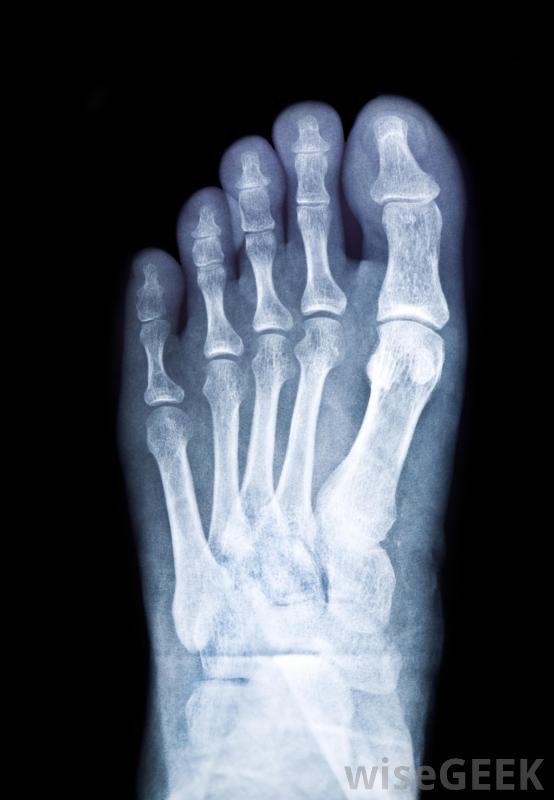

足踝外科醫生對腳和踝關節進行外科手術。這可能包括重建手術和整容手術。足踝外科醫生的一些手術也可能包括矯正足部畸形和修復外傷如果出現多處骨折,外科醫生在手術前可能需要做一次足部x光片。有一些特殊的設施,比如足踝診所,訓練有素的專家在那里治療他們的病人。足科醫生或足部外科醫生可以檢查和治療這些診所的病人。診所可以為不預約的病人提供治療,這對某些人來說更方便。腳后跟疼痛有時表明需要進行足部手術足踝外科醫生可能要做的一些主要手術是治療因受傷引起的骨折。腳趾骨折、腳踝骨折或足部骨折可能需要手術來修復。這通常被稱為矯形外科手術。一些足踝專家治療所有年齡段的人,還有一些專門從事兒科護理對于足部緩慢愈合的傷口,需要切除壞死組織的外科手術可能是一種治療方法,醫生可以對腳后跟進行x光檢查以確定病因。如果有嚴重骨折或足跟骨刺無法通過其他療程進行矯正,則可將患者轉診給足踝外科醫生。患者可能有開放性、閉合性或移位性跟骨骨折,外科醫生可以通過手術進行修復。手術對于恢復足部的完整功能和避免以后的并發癥是必要的。這些手術可能涉及骨骼平滑或移植。X光片可用于確定腳跟疼痛的原因。車禍或跌倒等事故可能會導致腳部或踝部受傷。可能會請足踝外科醫生或專家來評估情況。如果腳或踝關節有骨折或壓碎的骨頭,外科醫生可能需要通過外科手術來修復損傷。移除碎塊或碎骨是一種手術方法。可能還需要插入金屬針來固定骨頭前腳或腳趾的應力性骨折是足踝外科醫生可能治療的一種損傷。如果出現多處骨折或腳趾看起來有脫臼,外科醫生可能需要進行骨掃描和x光檢查。他可能會在手術前嘗試減輕腫脹一名高級足踝外科醫生可以利用他所在領域的最新技術和技術進步來治療病人。他通常獲得董事會認證,專門從事足踝重建手術。他還可以治療特殊需要的病例,例如糖尿病并發癥導致的足部傷口。在緩慢愈合的足部傷口中,需要切除壞死組織的外科手術可能是一種治療方法。扁平足的病人可以轉診給足踝外科醫生或專科醫生。外科醫生可以進行一種包括植入用于重新定位腳和腳踝的裝置。這將使行走時有更大的運動和放松。腳踝骨折的人。